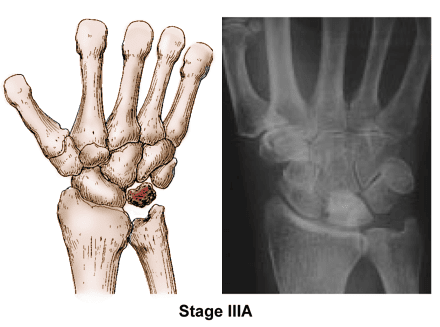

Stage III

• In Stage III, the necrotic or dead lunate bone begins to collapse and fragment (break) into pieces (Stage IIIA). As the bone begins to collapse or break apart, the surrounding bones become affected and may begin to shift position (Stage IIIB).

• During this stage, patients typically experience increasing pain, weakness in gripping, and limited wrist motion.

Kienböck's disease stage 3

Stage IIIA. Both the illustration and X-ray image show that the lunate has begun to collapse and several bones in the wrist have lost their normal alignment.